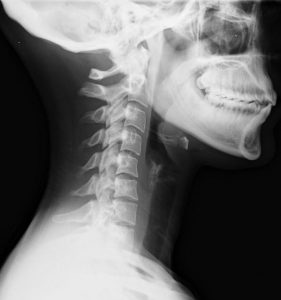

entorse cervicale, coup du lapin Publié le 3 janvier 20203 janvier 2020 par osteo-var Entorse cervicale, coup du lapin, cervicalgie, ostéopathe, gary monfort, le cannet des maures, le luc